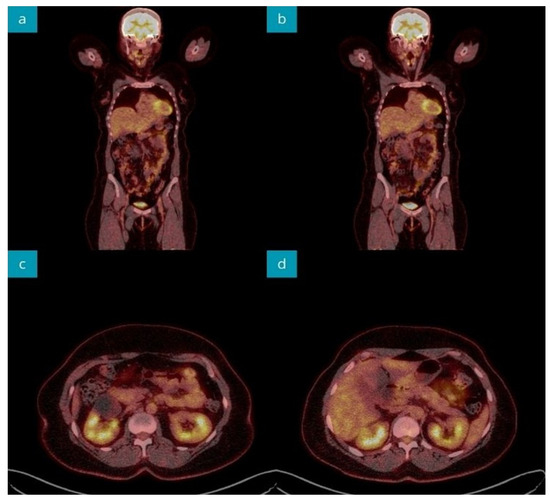

A computed tomography (CT) scan of the abdomen disclosed a normal pancreatic image and hepatic steatosis; however, a blind liver biopsy showed no abnormalities. An abdominal nuclear magnetic resonance imaging (MRI) revealed a mildly increased pancreatic dimension with fine-point areas of fluid signal, accompanied by normal serum amylase and lipase activities. The patient underwent MR-cholangiopancreatography (MRCP) without visualizing biliary and pancreatic pathology. Due to the unclear image of the pancreas, the diagnostic work-up was completed by performing an 18F-fluorodeoxyglucose positron emission CT (18F-FDG PET-CT) imaging, which did not visualize pathological 18F-FDG uptake (Figure 2). The patient received the AstraZeneca® COVID-19 booster in May 2019. At that time, no association between vaccination and pancreas pathology was established in the patient.

Figure 2.

18F-FDG PET-CT imaging during the primary diagnostic process revealed abdominal organs without pathological 18F-FDG uptake. Coronal sections (a,b). Axial sections of pancreatic head (c), body, and tail (d).